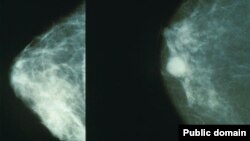

Кўкрак маммограммаси: соғлом кўкрак (чапда) ва саратонга салинган кўкрак.